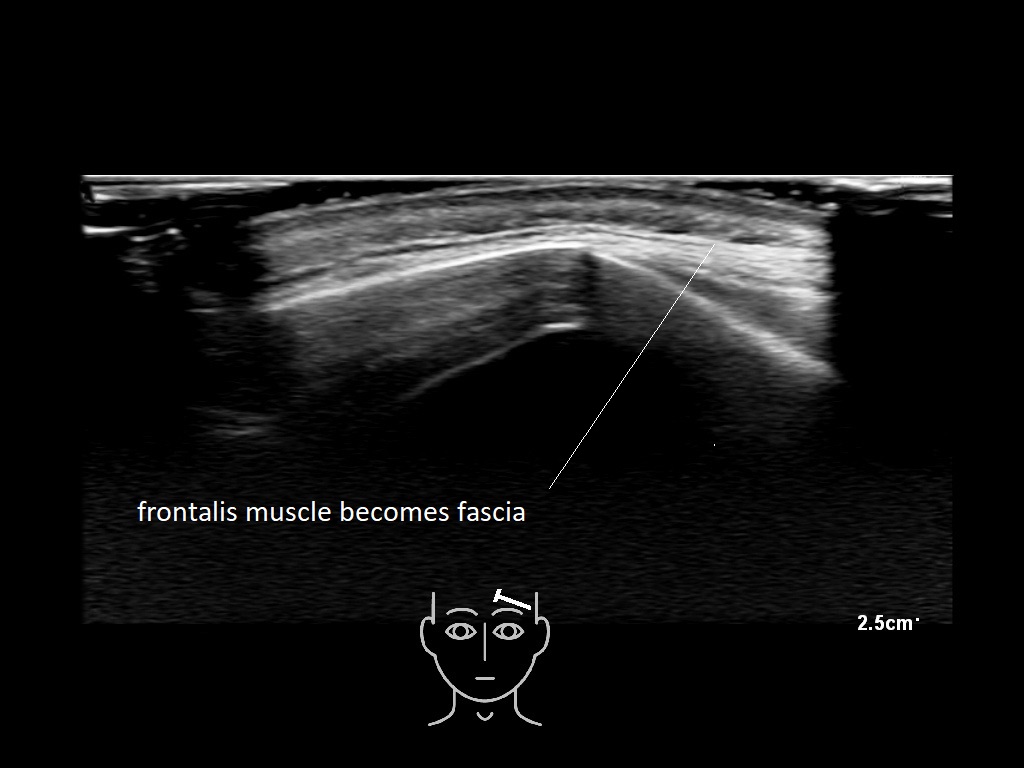

The forehead

In this section you will learn more about the different layers of the face with the use of ultrasound. When you click on the secondary ultrasound image, you will see the different structures as an overlay. This will help to train yourself to recognize the different layers of the face.

Study the first image to recognize the different layers. If you are sure about the layers, swipe to the second image to view the answer (if applicable).